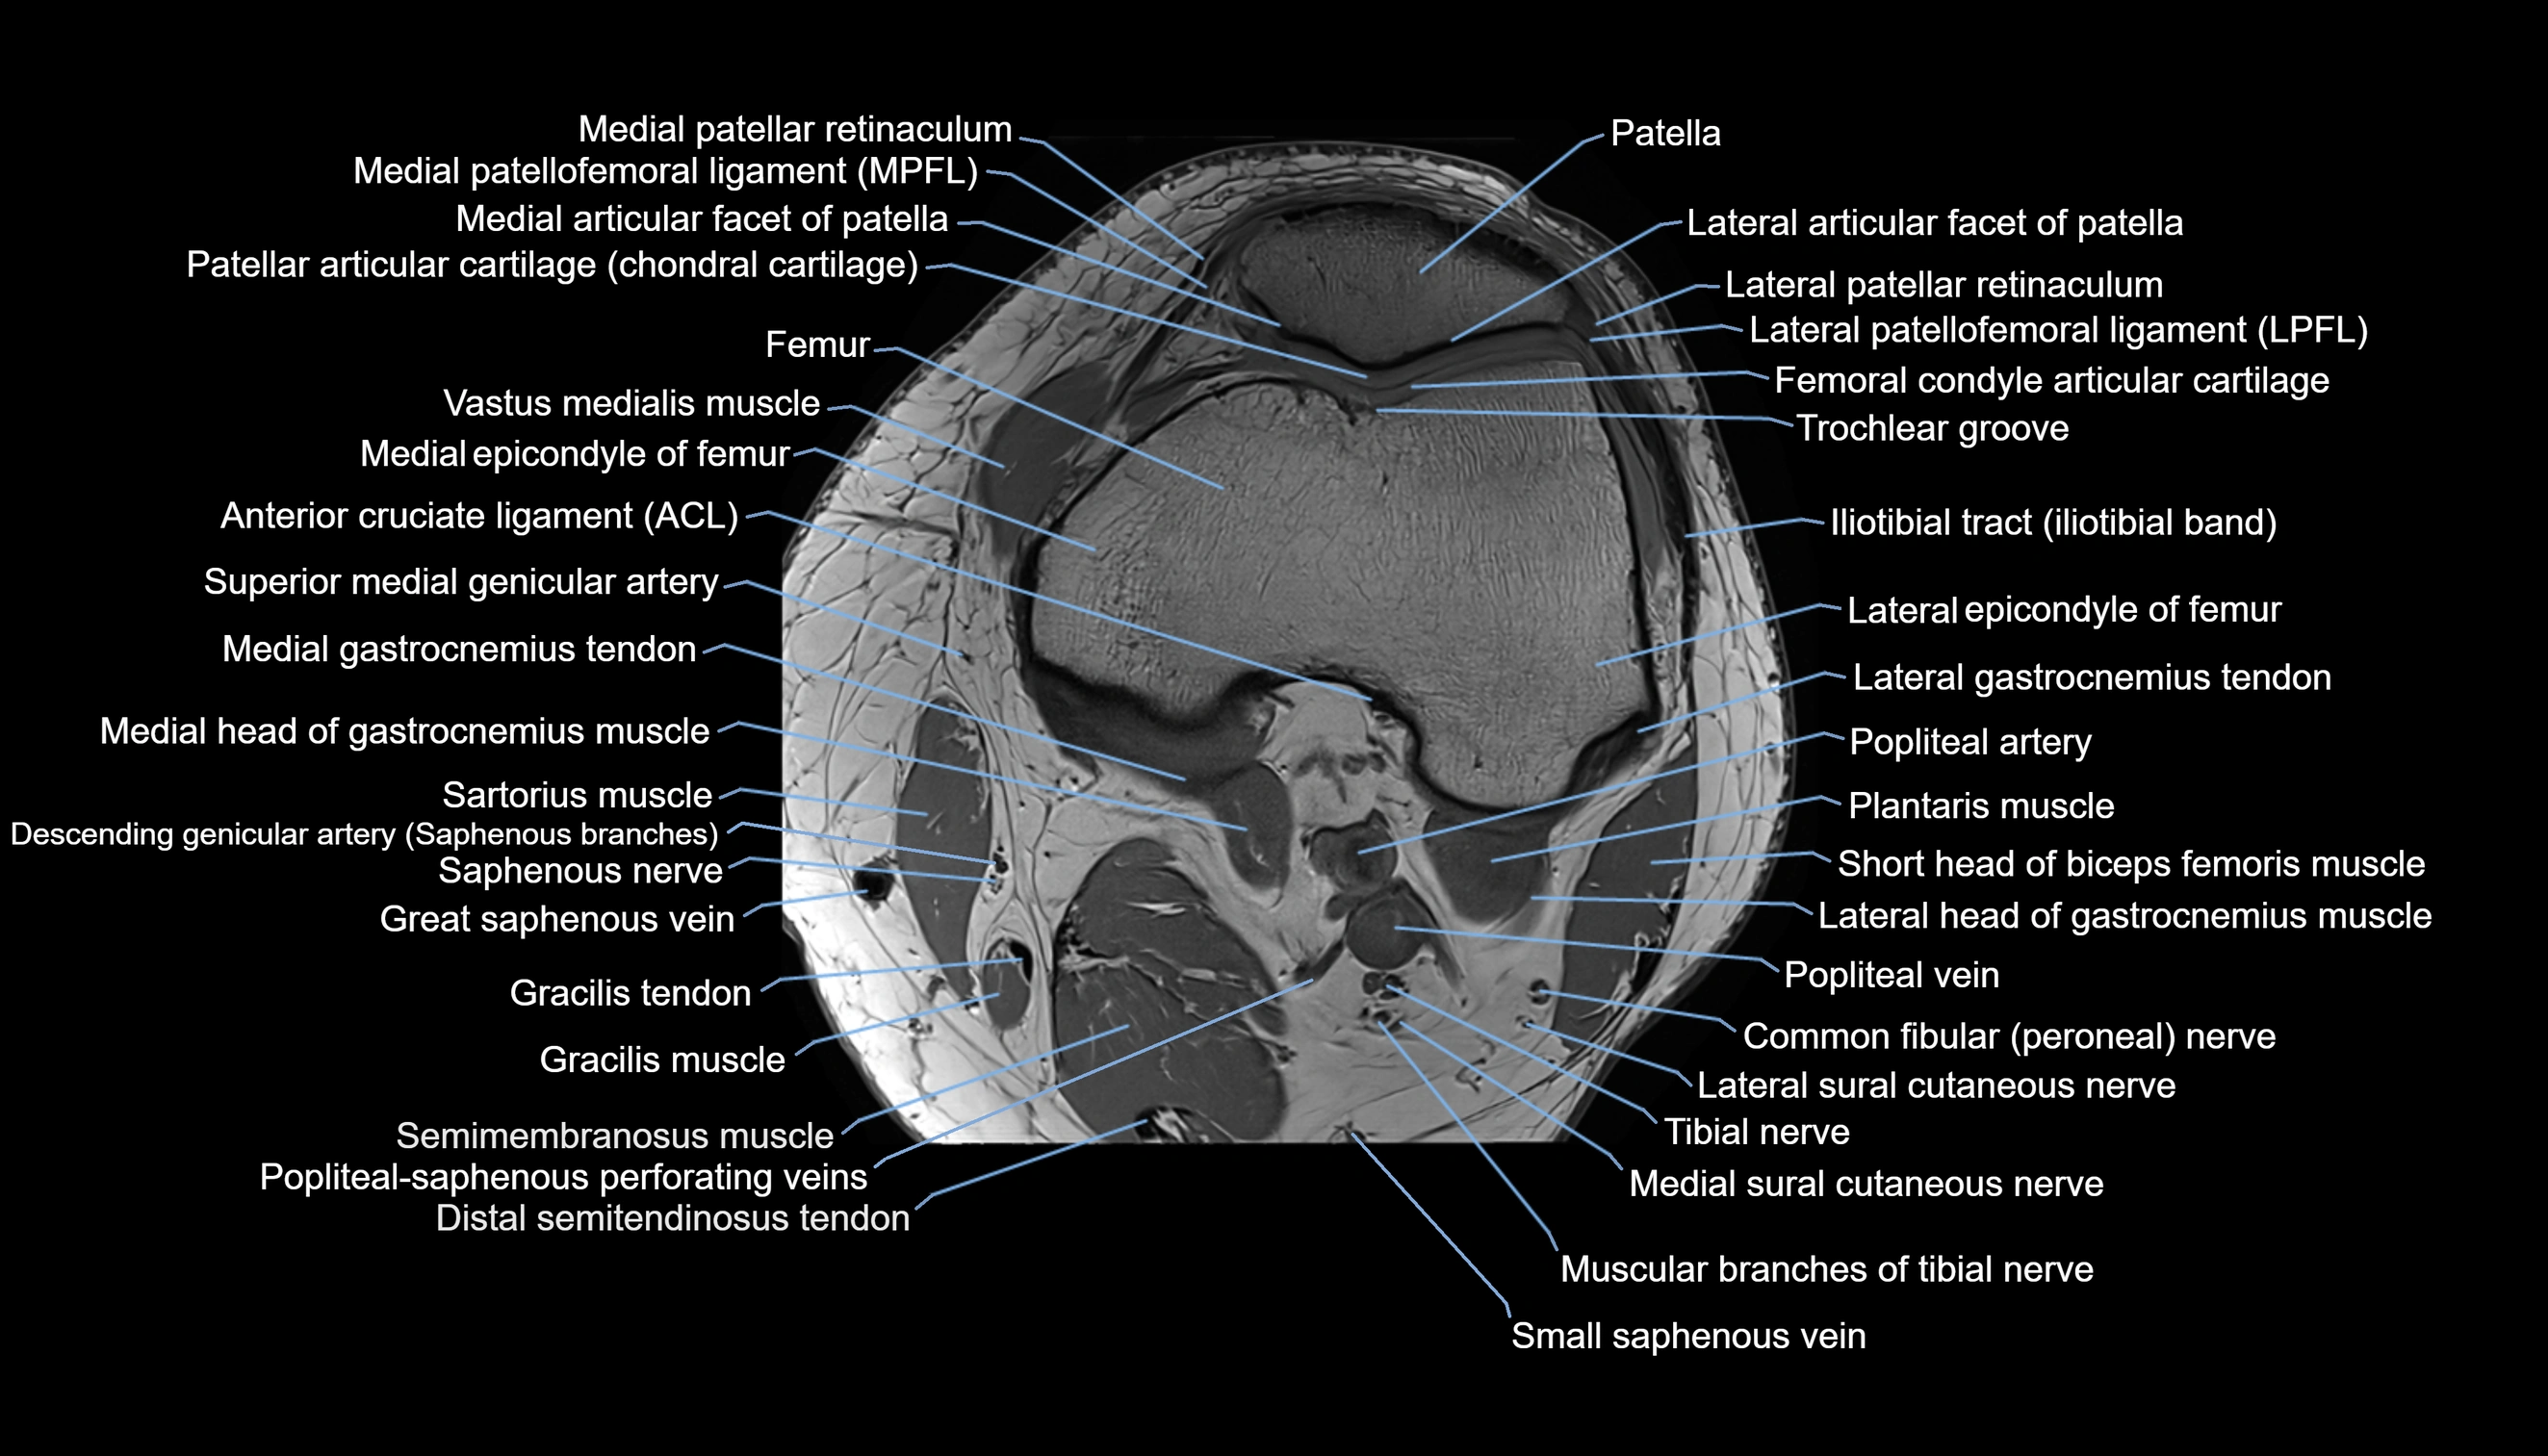

- Anterior cruciate ligament

- Common fibular nerve

- Femoral condyle articular cartilage

- Lateral articular facet of patella

- Lateral epicondyle of femur

- Lateral gastrocnemius tendon

- Lateral head of gastrocnemius muscle

- Lateral patellar retinaculum

- Lateral patellofemoral ligament

- Lateral sural cutaneous nerve

- Medial articular facet of patella

- Medial epicondyle of femur

- Medial gastrocnemius tendon

- Medial head of gastrocnemius muscle

- Medial patellar retinaculum

- Medial patellofemoral ligament

- Medial sural cutaneous nerve

- Muscular branches of tibial nerve

- Patella

- Patellar articular cartilage

- Popliteal artery

- Popliteal vein

- Saphenous nerve

- Sartorius muscle

- Semimembranosus muscle

- Small saphenous vein